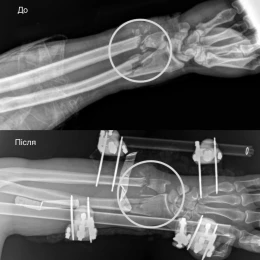

Стан був украй важкий: рука трималася фактично лише на шкірі. Артерії були повністю перерізані, кістки зламані, пошкоджені м’язи, сухожилля та нерви. За порятунок кінцівки взялася команда лікарів різних спеціальностей.

Спочатку травматологи зафіксували переломи спеціальним апаратом. Потім судинні хірурги відновили кровообіг, зшили пошкоджені судини.